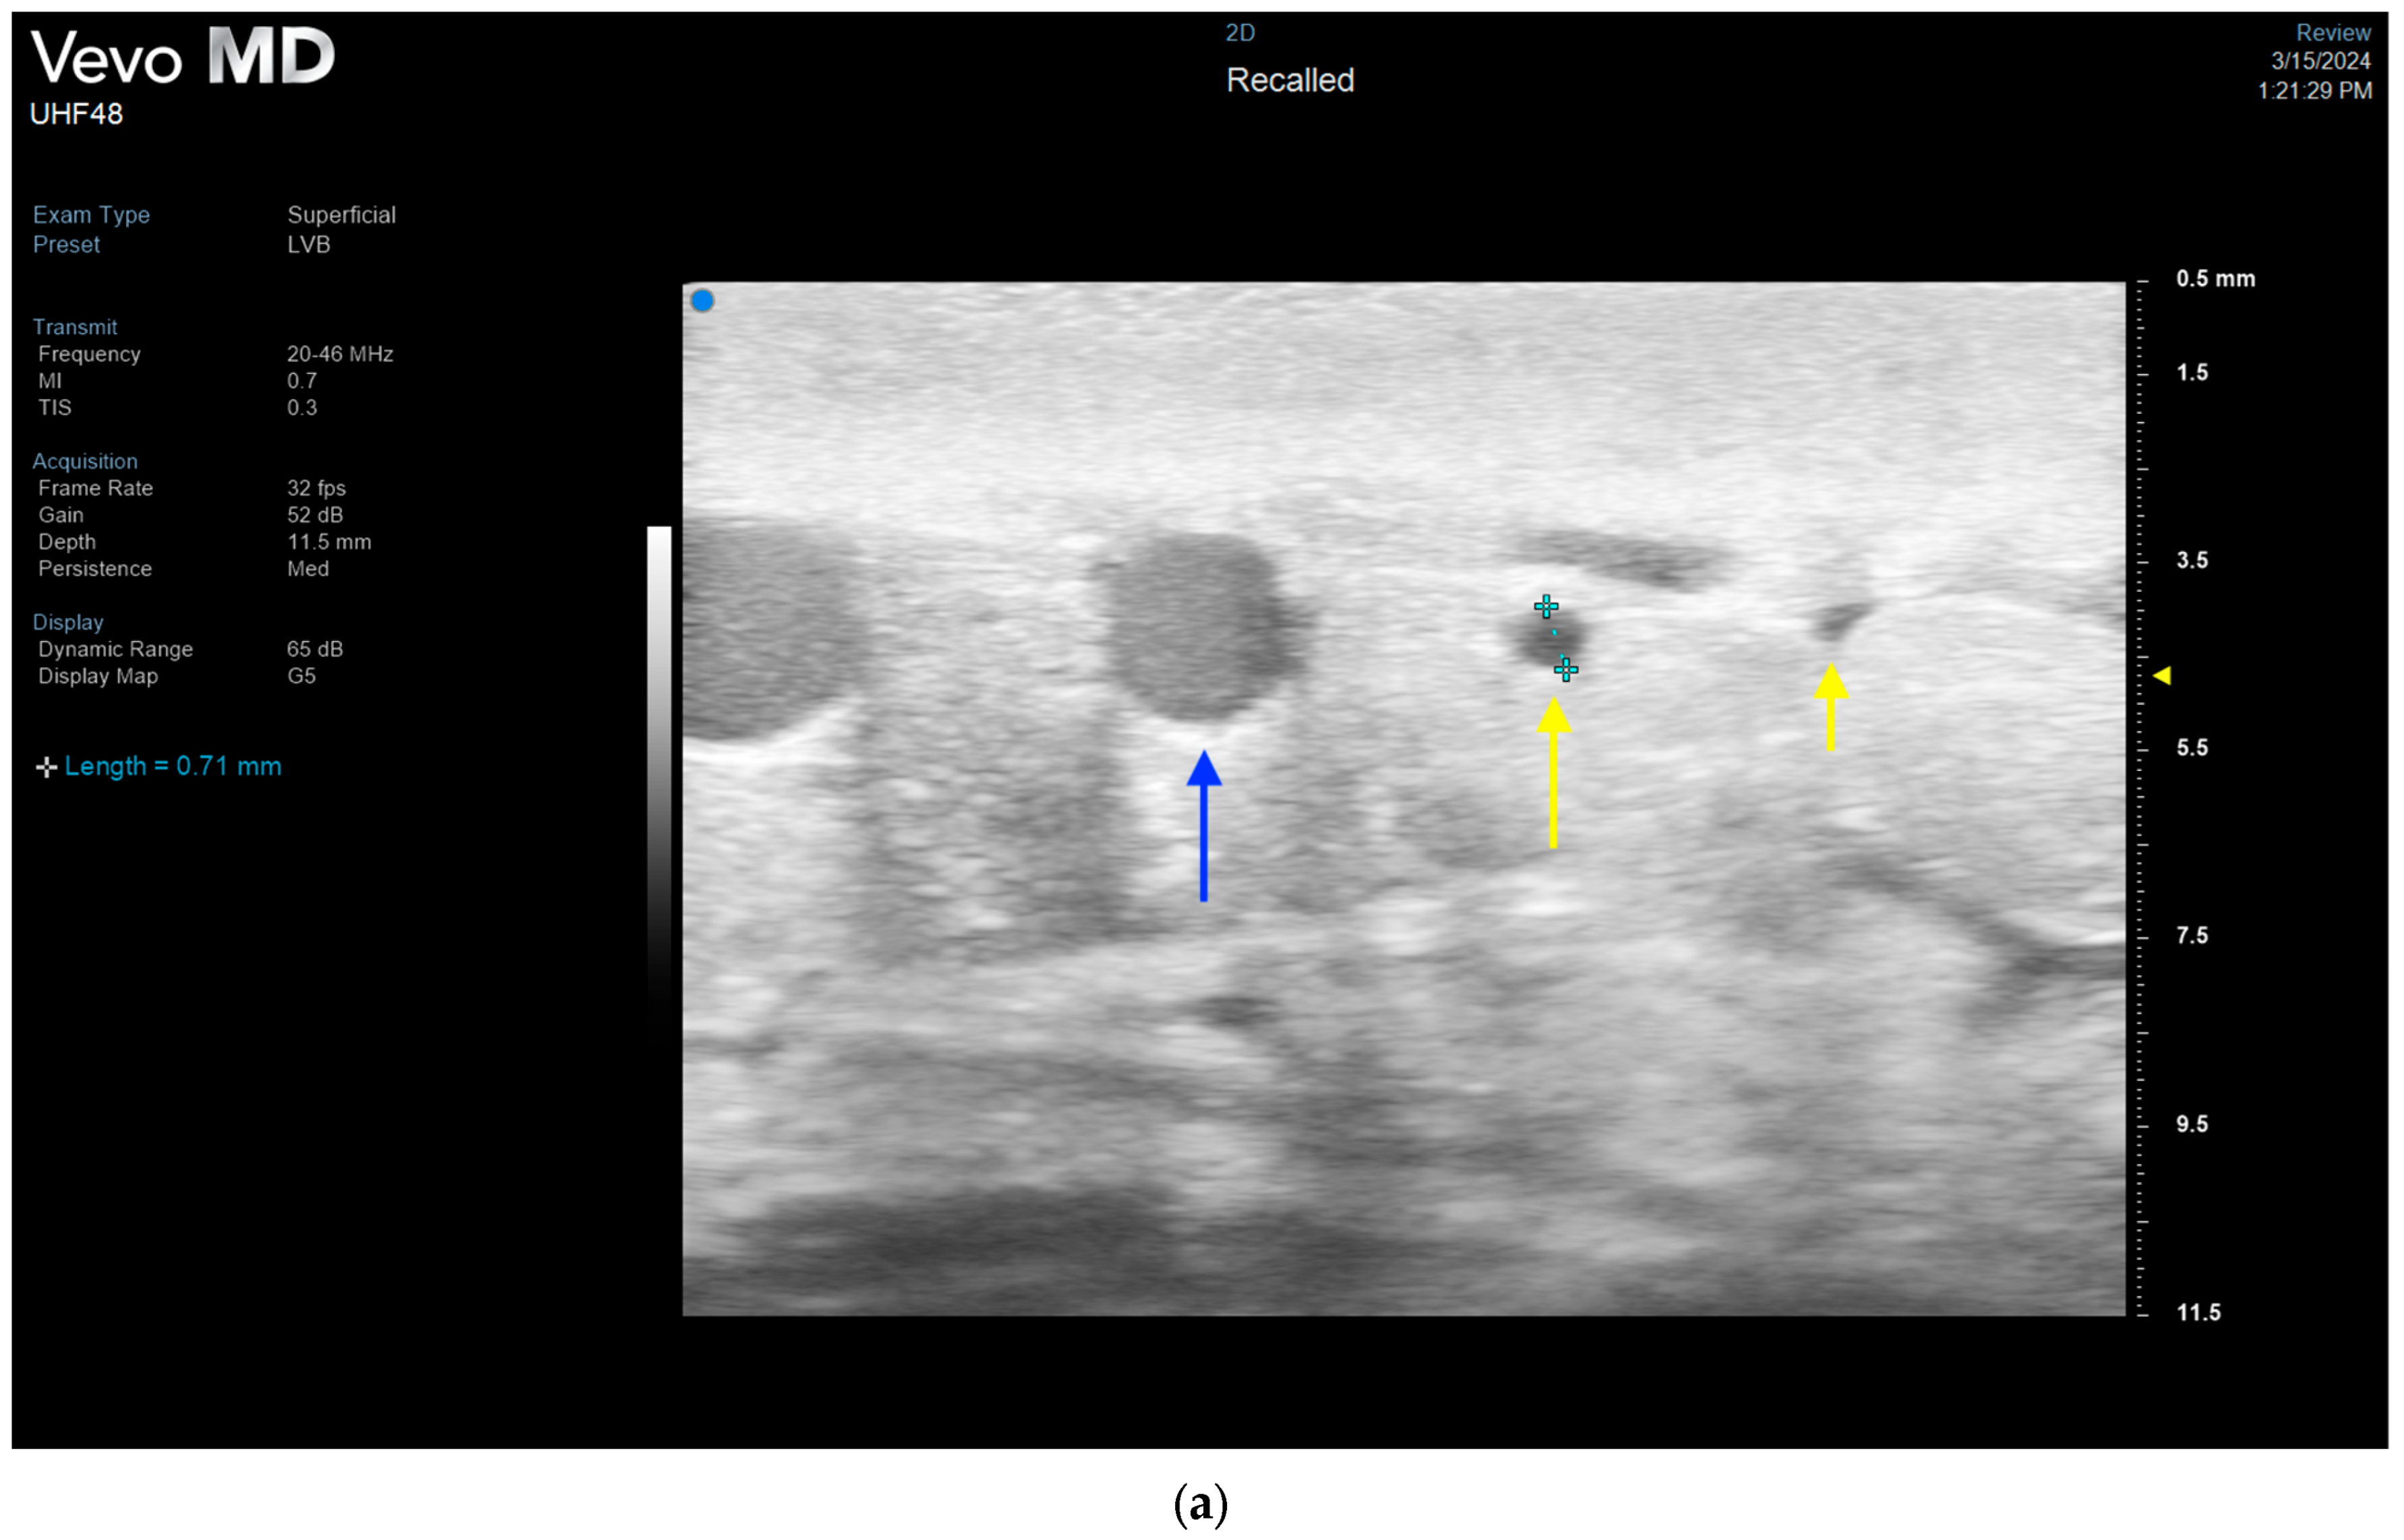

3.4. Lymphatic Surgery

- Hayashi, A.; Giacalone, G.; Yamamoto, T.; Belva, F.; Visconti, G.; Hayashi, N.; Handa, M.; Yoshimatsu, H.; Salgarello, M. Ultra High-frequency Ultrasonographic Imaging with 70 MHz Scanner for Visualization of the Lymphatic Vessels. Plast. Reconstr. Surg.-Glob. Open 2019, 7, e2086. [Google Scholar] [CrossRef] [PubMed]

- Hayashi, A.; Visconti, G.; Giacalone, G.; Hayashi, N.; Yoshimatsu, H. Recent Advances in Ultrasound Technology: Ultra-High Frequency Ultrasound for Reconstructive Supermicrosurgery. J. Reconstr. Microsurg. 2022, 38, 193–199. [Google Scholar] [CrossRef] [PubMed]

- Bianchi, A.; Visconti, G.; Hayashi, A.; Santoro, A.; Longo, V.; Salgarello, M. Ultra-High frequency ultrasound imaging of lymphatic channels correlates with their histological features: A step forward in lymphatic surgery. J. Plast. Reconstr. Aesthetic Surg. 2020, 73, 1622–1629. [Google Scholar] [CrossRef] [PubMed]

- Czedik-Eysenberg, M.; Steinbacher, J.; Obermayer, B.; Yoshimatsu, H.; Hara, H.; Mihara, M.; Tzou, C.J.; Meng, S. Exclusive use of ultrasound for locating optimal LVA sites—A descriptive data analysis. J. Surg. Oncol. 2019, 121, 51–56. [Google Scholar] [CrossRef] [PubMed]